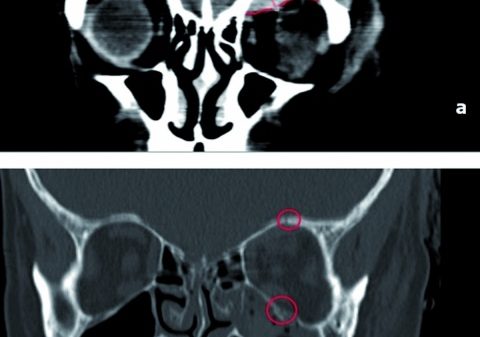

Aufgrund der engen Lagebeziehung zu neurovaskulären Strukturen sind Raumforderungen der Augenhöhle oder im Bereich der orbitanahen Schädelbasis in Bezug auf Diagnostik und Therapie eine besondere Herausforderung. In Abhängigkeit von Entitäten und Lokalisation können verschiedene Behandlungsansätze, wie zum Beispiel eine Operation oder auch ein konservatives Vorgehen, in Frage kommen.

In diesem Beitrag werden anhand ausgesuchter Fallbeispiele die Besonderheiten verschiedener Neoplasien in dieser Region und die jeweils spezifische Therapie vorgestellt und diskutiert. Dies soll den interdisziplinären Ansatz am Kopfzentrum des BundeswehrZentralkrankenhauses Koblenz verdeutlichen, der für einen therapeutischen Erfolg von großer Bedeutung ist.

Die Orbita ist pyramidenförmig gebaut und durch verschiedene Strukturen begrenzt. So sind die Ossa frontale, temporale, zygomaticum, maxillare, ethmoidale, sphenoidale, palatinum und lacrimale an der knöchernen Begrenzung beteiligt. Die Augenhöhle hat außerdem multiple Durchtrittsstellen und beherbergt Faszien, die Augenmuskeln, den Bulbus, die Tränendrüsen, Gefäße und Nerven. Zum besseren Verständnis der Orbita muss diese in einen Extrakonalraum, Intrakonalraum, subperiostalen und den präseptalen Raum aufgeteilt werden, da die verschiedenen Entitäten typische Lokalisationen bieten. Dabei bezeichnet der Intrakonalraum den dorsal des Bulbus gelegenen, konisch zulaufenden Raum innerhalb der geraden Augenmuskeln; hier verlaufen der N. opticus, die A. ophtalmica sowie die Vv. ophtalmicae sup. et inf. sowie die Nn. ciliares breves.